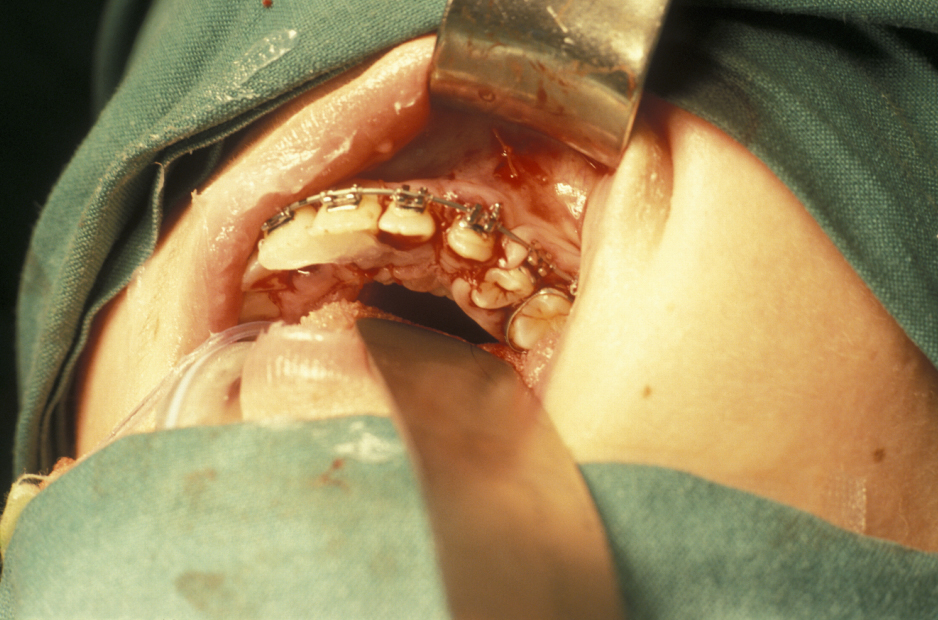

- Buccal Flap – a full thickness mucoperiosteal flap is raised from the buccal surface of the wisdom tooth area. The choice of incision varies, but commonly involves an incision along the external oblique ridge passing forward either around the second molar tooth or out into the buccal sulcus (Figure 3). If little or no bone is to be removed, a simple relieving incision may be all that is necessary. The important point is that dissection proceeds in a subperiosteal plane as this minimises postoperative swelling and trismus (Figure 4).

- Bone removal – this is usually done with either a burr (Figure 6) or (rarely now) chisels. A piezoelectric saw has been used but much less commonly. How much bone needs to be removed depends on the position of the tooth. Care is required to ensure that enough bone remains to support the second molar tooth. If chisels are used, mesial and distal stop cuts need to be placed to prevent fracture propagation (Figure 7).

- Tooth removal – in less impacted cases a point of application may be drilled into the tooth, which is then elevated out of the socket (Figure 8). It is important not to lever the tooth out as any resistance may change the fulcrum of elevation and result in the inferior dental nerve being crushed. If the tooth does not elevate it may be better to divide it and remove it in pieces. This is where the unprotected lingual nerve may be damaged if the burr is passed too deeply.